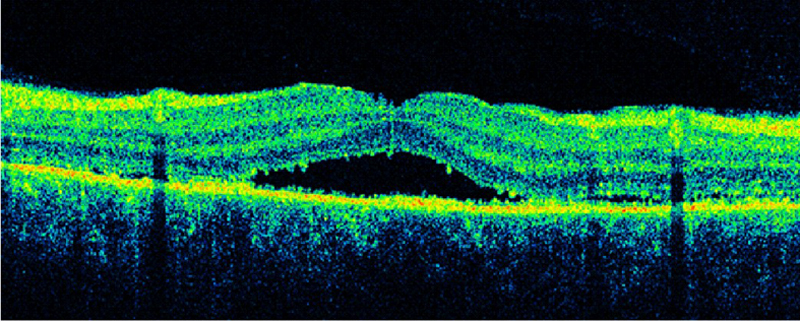

Edema macular quístico (EMQ): presencia de espacios quísticos intraretinianos hiporreflectivos claramente definidos, separados por septos finos de tejido retiniano de alta reflectividad.

Desprendimiento de retina seroso (DRS): con acumulación de fluido entre el epitelio pigmentario de la retina y la retina neurosensorial.

3-5. Tanto el EMQ como el EMD pueden asociarse a DRS (

Tabla 2 y

Figura 4,

Figura 5,

Figura 6 y

Figura 7).

Tabla 2. Características de OCT de los 3 subtipos de edema macular.

Figura 4. Edema macular quístico (EMQ).

Figura 6. Desprendimiento de retina seroso (DRS) en una paciente con uveítis asociada a enfermedad de Behçet.

Figura 7. Desprendimiento de retina seroso subfoveal asociado a edema macular quístico en una paciente con coroidopatía tipo Birdshot.